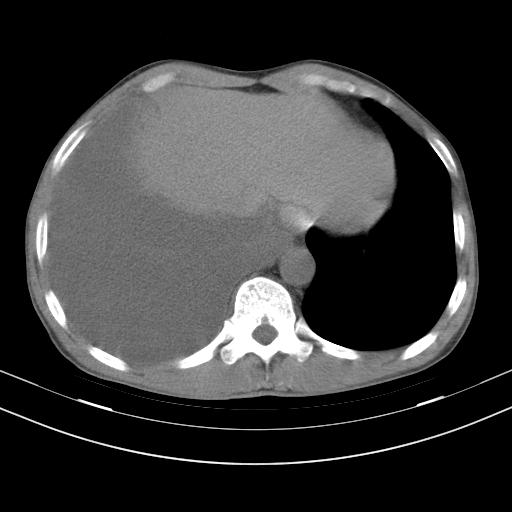

男性,44岁,结核病史多年。现胸闷气短,咳嗽,偶咳血。

右侧胸腔积液

右肺下叶不张

双肺多发结节影最分空洞形成考虑占位不除外结核

双肺陈旧性病变

1、右侧大量胸腔积液伴右肺压缩性膨胀不全,建议抽液治疗后复查 2、两肺继发性tb伴空洞形成。

1)两肺继发性肺结核伴空洞形成,左肺多发性结核球。2)右侧大量胸腔积液伴右肺部分膨胀不全。3)纵隔淋巴结肿大。

1,双肺多发结节 并空洞影改变, 左侧胸腔积液并部分包裹, 结合原病史首先考虑结核. 但也不除外其它.

2,左侧有一根肋骨陈旧性骨折? 建议追查 .

吉大一院胸水抽检结果:结核性胸水